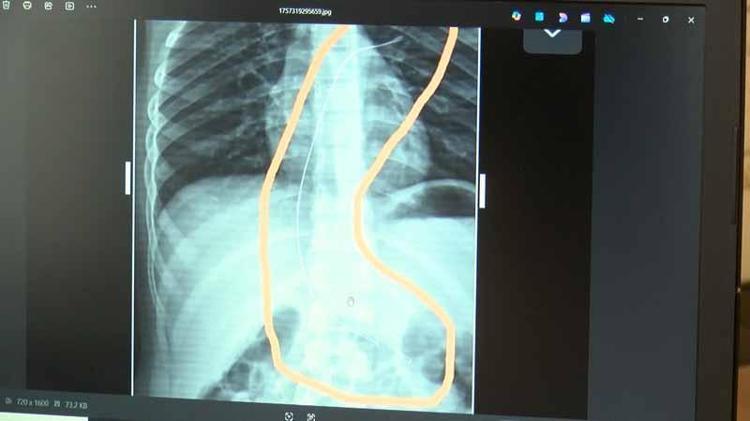

Şırnak’ta piknikte salatalık parçası yuttuktan sonra öksürük ve kusma şikayetleriyle hastaneye götürülen Aram Devran Ötün’ün (6), 3 yıl önce Stevens- Johnson sendromu nedeniyle tedavi gördüğü sırada damar yoluna takılan 18 santimetrelik kateterin vücudunda unutulduğu ortaya çıktı. Öğüt, 5,5 saat süren riskli bir ameliyatla kateterden kurtuldu.

Şırnak’ta yaşayan Semra (37) ve Mehmet Ötün (40) çiftinin oğulları Aram Devran Ötün, mayıs ayında piknikteyken salatalık parçası yuttuktan sonra öksürük ve kusma şikayetleri görülünce Şırnak Devlet Hastanesi’ne götürüldü. Burada çekilen röntgen ve MR’da Aram’ın vücudunda kateter unutulduğu görüldü. Diyarbakır’daki Gazi Yaşargil Eğitim ve Araştırma Hastanesi Kadın Doğum ve Çocuk Ek Binası’na sevk edilen Aram, 5,5 saat süren riskli bir ameliyata alınarak 18 santimetre uzunluğundaki kateter çıkarıldı. Ameliyat sonrası yapılan incelemelerde kateterin kalp kapakçığına ve ciğerlerine zarar verdiği belirlendi.

Ailenin avukatı Ahmet Yalçın, hastane hakkında hem şikayetçi olduklarını hem de dava açtıklarını belirterek, “Müvekkilim Aram Devran Ötün, 2022 Eylül ayında Dicle Üniversitesi Hastanesi’nde Stevens- Johnson hastalığı nedeniyle tedavi gördü. Tedavi sırasında kendisine kateter takıldı. 18 santimetre uzunluğundadır. Bunu takarken büyük bir ihmalkarlık yapılarak vücudunda unutuldu. Mayıs ayında müvekkilim çok öksürdüğü için Şırnak Devlet Hastanesi’ne kaldırıldı. Burada yapılan tetkiklerde kateterin unutulduğu tespit edildi. Daha sonra Diyarbakır Gazi Yaşargil Kadın ve Çocuk Hastalıkları Hastanesi’ne götürüldü. Çok riskli bir ameliyata alındı ve kateter çıkarıldı. Bu kateterin vücutta yol aldığı tespit edildi. İlk giriş yeri ve çıkarıldığı yer arasında çok fark var ve kalp kapakçığı ile ciğerlerine zarar verdiği tespit edildi. Müvekkillerimin hem maddi hem de manevi zararlarını karşılamak adına Dicle Üniversitesi’ne biz başvuruda bulunduk. 30 günlük cevap süresi içerisinde bize geri dönüş yapılmadı. Biz de maddi ve manevi zararların tazminat için Diyarbakır İdare Mahkemesi’ne davamızı açtık ve sorumlulardan şikayetçi olduk” dedi.

Oğlunun piknikte salatalık parçası yuttuktan sonra sürekli öksürmeye ve kusmaya başladığını söyleyen Semra Ötün, “Çocuğum 3 yıl önce Steven Johnson sendromu hastalığına yakalandı. Milyonda bir görülen antibiyotikten kaynaklı bir hastalık. Doktorlar öyle söyledi. Bizi acilen Diyarbakır Dicle Üniversitesi Çocuk Hastanesi bölümüne sevk ettiler. 1 ay yoğun bakım sürecimiz oldu. 28 gün yoğun bakımda, 3 günde serviste kaldı. Damar yolundan, kasıktan serum taktılar. Kateter denilen tel çocuğun vücudunda bırakılıyor. Biz taburcu olduğumuzda fark edilmiyor. 3 yılın sonunda biz bunu fark ettik. Pikniğe gittik. Oğlum salatalık parçası yuttu ve salatalık parçasından sonra akşama kadar öksürdü. Hiçbir şekilde durmadı. Kusuyordu. Ben şüphelenmeye başladım. Çocuğum normal değildi. Sonra eşime danıştım. Akşam 21.00 civarında acile götürdük. Röntgeni ve MR’ı çekildi. Tuhaf bir şey olduğunu anladık. Doktor röntgeni gösterdi. Tel kalmıştı. Çok kötü bir şekilde. Acil doktoru film çektikten sonra bize bir tel parçasını gösterdi. Bizi bekletmeden Diyarbakır’a sevkimizi verdiler. Diyarbakır Gazi Yaşargil Eğitim ve Araştırma Hastanesi Kadın Doğum ve Çocuk Ek Binası’na gittik. Çocuğun kasıklarından anjiyo yolu ile teli çıkaracaklarını ama riskli bir ameliyat olduğunu söylediler. O süreçte çocuk gerçekten sürekli yoruluyordu. İkide bir oturuyordu. ‘Anne çok yoruldum, karnım ağrıyor’ diyordu. Ben ağrı kesiciler ile geçiştirmeye çalışıyordum. Bu telin 3 yıl boyunca çocuğumda kaldığını öğrendim. Ailece yıkıldık” diye konuştu.